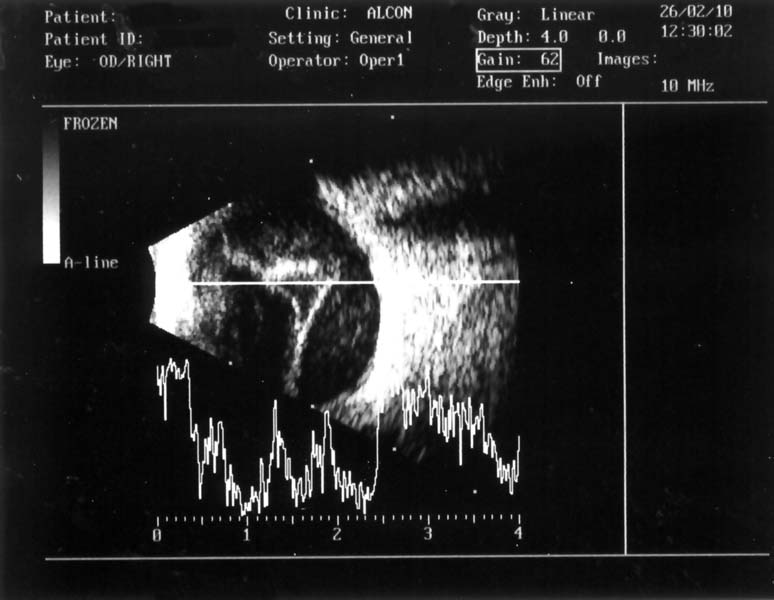

• Vyšetřit oko ultrazvukem

Vyšetření oka ultrazvukem